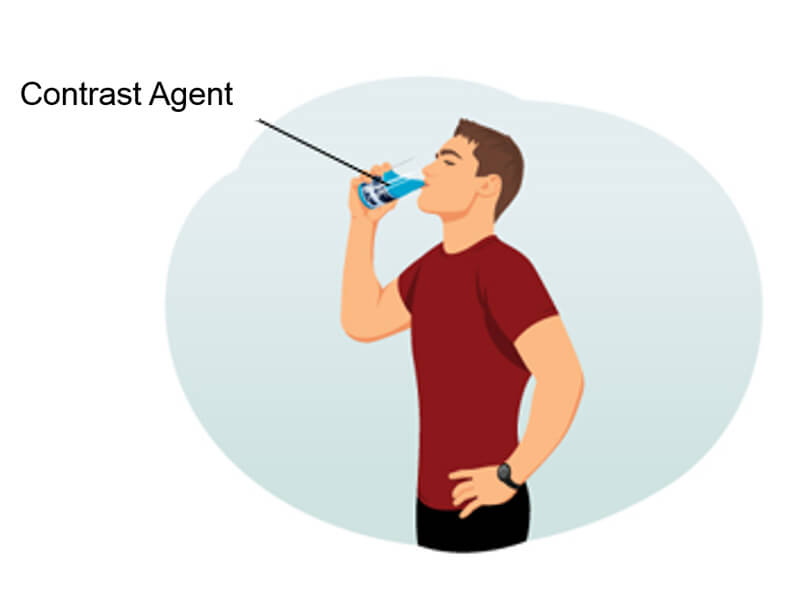

Other Contrast Agents

On this slide, we find a non-exhaustive list of various contrast agents that can be used in MRI. We also note that certain contrast agents used are completely natural, and they are not all administered intravenously. Examples of natural contrasts are:

- Water, which is given orally

- Air which is given orally

- Blueberry Or pineapple juice which is given orally

Some examples of artificial contrast are:

- Telescan

- Lumirem

- Methylcellulose

- Vaseline or ultrasound gel

Oral Contrasts

As you can tell from this list, each has different applications and can be used for various reasons. But all serve the same basic purpose. To provide some type of contrast to the scan. Contrast agents can be classified in various ways. Here are some examples of oral contrasts.